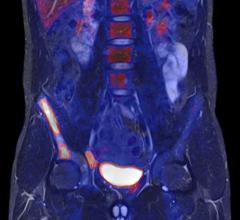

The ITM Group announced that its subsidiary ITG GmbH has successfully in-licensed DOTA-Zoledronate, a next-generation theranostic agent for bone targeted radionuclide therapy and diagnostics in patients suffering from bone metastases. DOTA-Zoledronate specifically targets cancerous bone lesions and, when radiolabeled with therapeutic or diagnostic radioisotopes, has shown high potential for positron emission tomography (PET) imaging and endoradiotherapy.